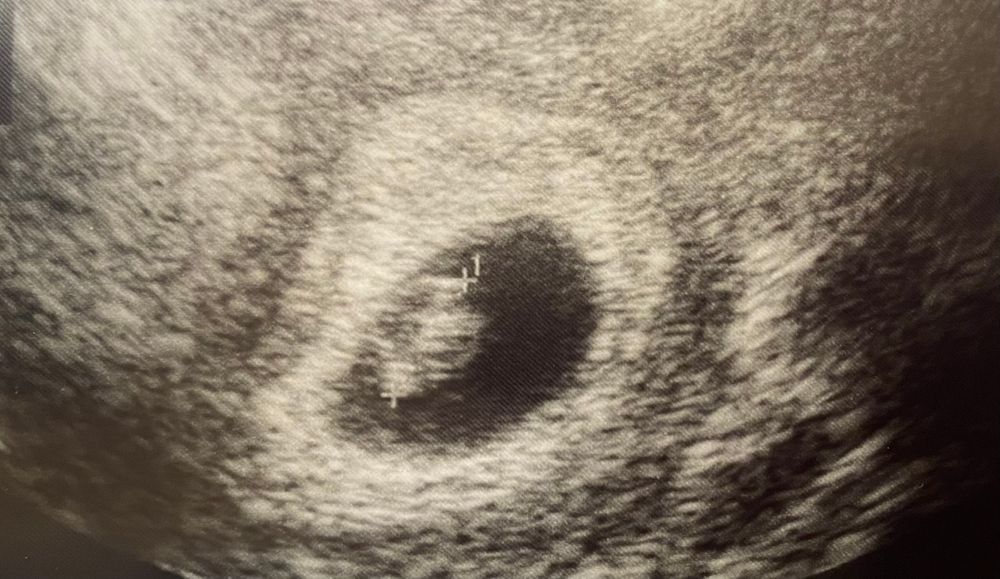

7+2, узи

ES, да на узи ходила получаеться 6 недель 4 дня ) эти сроки по узи ) по акушерским у меня 9 недель ) поздняя овуляция